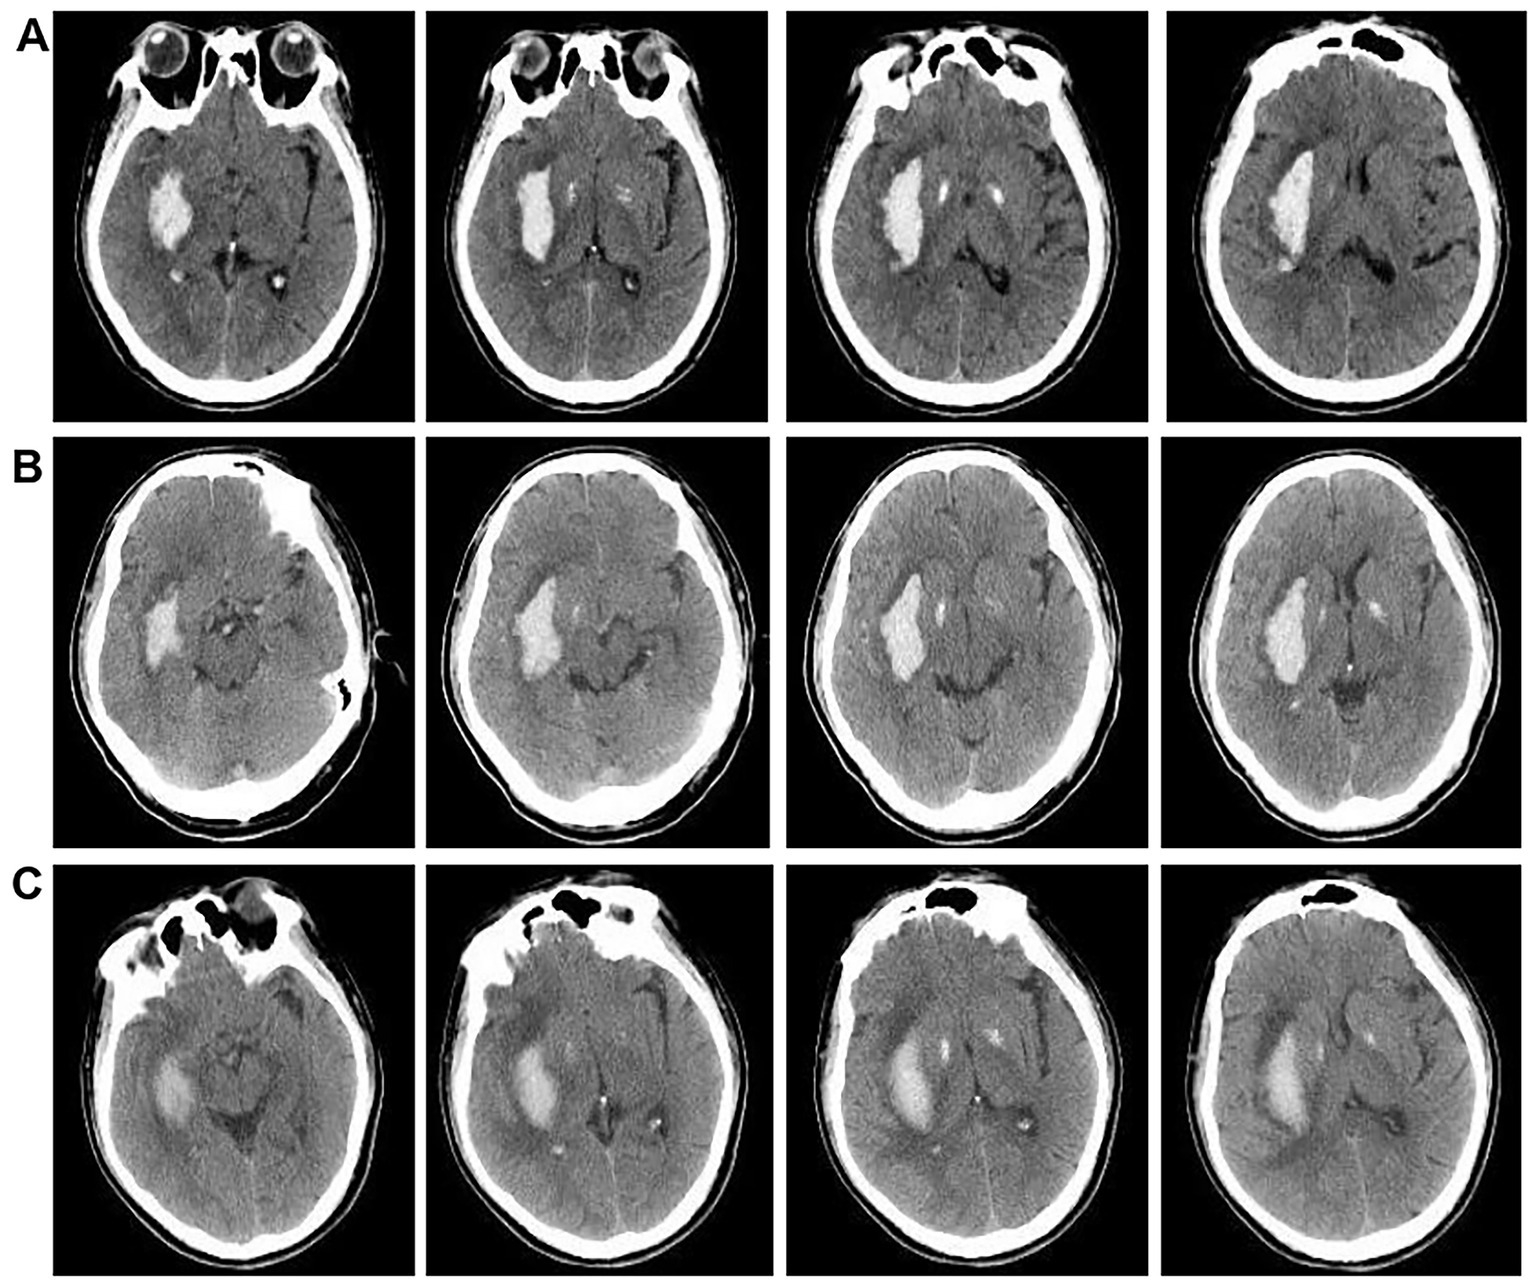

Figure 3

CT comparison images before and after surgical intervention. (A) Brain CTA scan images of patients upon admission. (B) Brain CT scans of patients 24 h post-surgery. (C) Brain CT scans of patients 3 days post-surgery.

When significant resistance is encountered or the volume of hematoma removed reaches 60%, the procedure is concluded by ceasing suction of the hematoma and securing the drainage tube. Subsequently, urokinase thrombolytic therapy is administered. This involves dissolving 20,000 units of urokinase in 2.0 mL of 0.9% saline solution and infusing it into the hematoma cavity via the drainage tube. The drainage tube is then closed, and urokinase is retained for 2–3 h. Afterward, the drainage tube is reopened to drain the urokinase and liquefied hematoma. This procedure is performed 2–3 times daily for 2–5 days. Urokinase thrombolytic therapy was immediately discontinued, and the drainage tube was removed once the cerebral hematoma had completely resolved. The absorption of cerebral haematoma was monitored by the first brain CT scan within 24 h after surgery (Figure 3B) and subsequent CT scans every 2–3 days, depending on the patient’s condition (Figure 3C). Other treatment measures and pharmacological interventions were consistent with the medication intervention group, with specific details as follows.